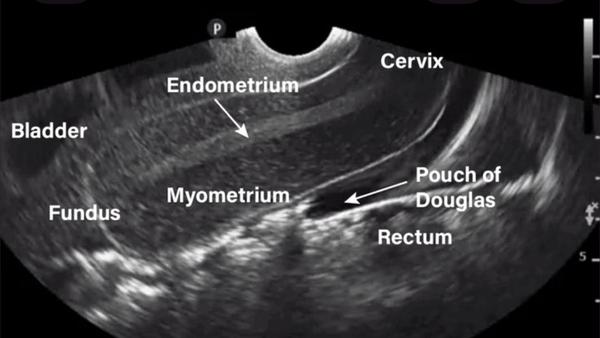

HSG (Hysterosalpingogram ) in rohini delhi

HSG (Hysterosalpingogram ) in rohini delhi HSG test near me C-8/193 sec 8 rohini delhi 9811552...